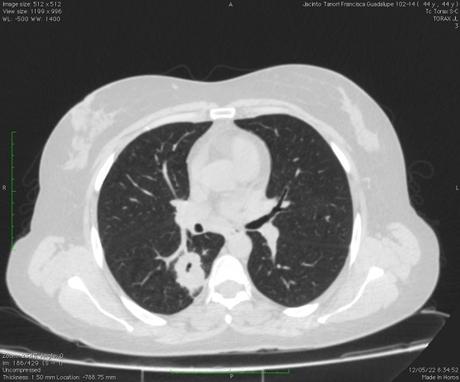

Vía aérea y pulmones: Con ventana para pulmón se observa hacia el segmento superior del lóbulo inferior derecho la presencia de una lesión cavitada, la cual tiene un diámetro máximo de 3.3 cm, además ambos pulmones presentan algunas áreas con patron micronodular, predominantemente hacia lóbulos medio y língula. La tráquea se aprecia central, sin alteraciones.

- ESTUDIO TOMOGRÁFICO DE TORAX QUE MUESTRA HALLAZGOS QUE PUDIERAN CORRESPONDER CON PROCESO INFECCIOSO DE TIPO GRANULOMATOSO NO TUBECULOSO (MICOBACTERIUM AVIUM) COMO PRIMERA POSIBILIDAD, SIN EMBARGO, LA POSIBILIDAD DE QUE PROCESO TUBERCULOSO O FIMICO NO PUEDE SER DESCARTADO.